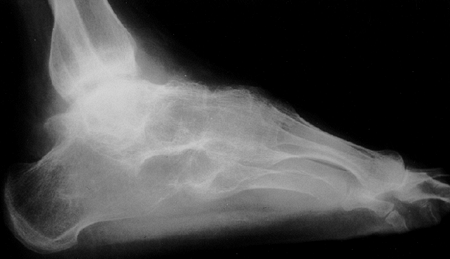

deposition of monosodium urate crystals into the joint. The major

clinical manifestations include acute mono- or oligoarthritis,

frequently involving the first metatarsophalangeal joint, resulting in

podagra. Gout may result from either increased production or decreased

excretion of uric acid. Gout is extremely rare in children (29).